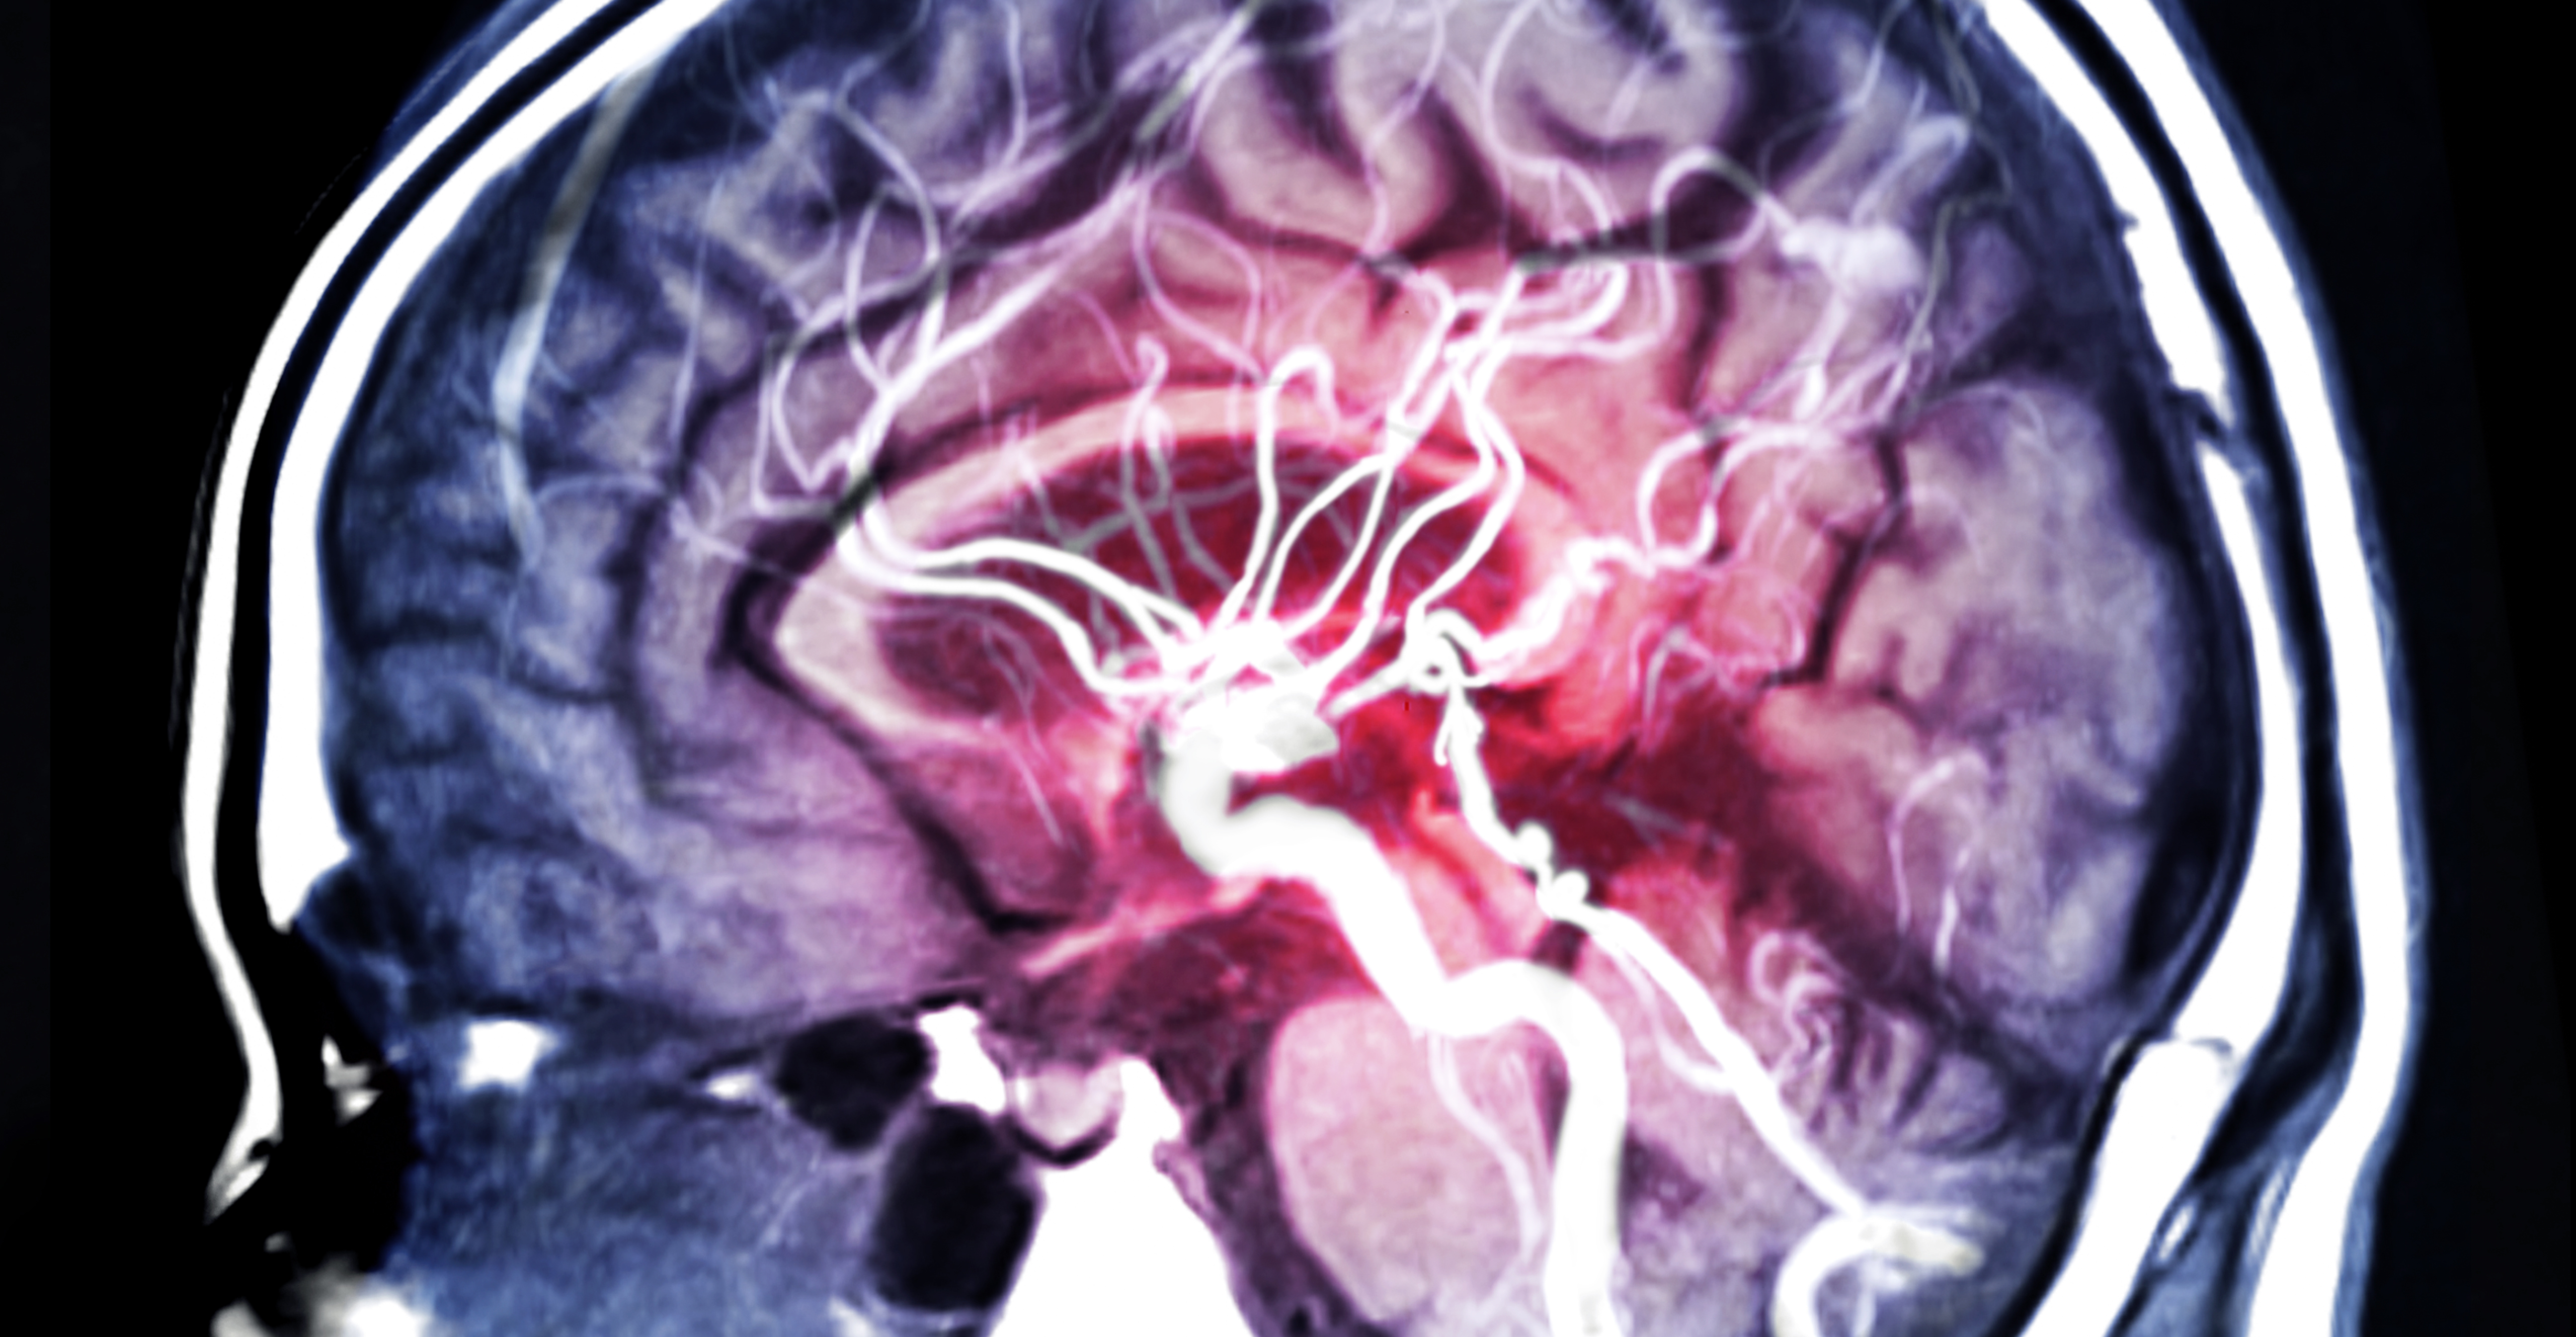

Un traitement antioxydant de l’AVC ischémique aigu pourrait retarder l'apparition de la maladie d'Alzheimer, conclut cette recherche d’une équipe de l’Université d’Oradea (Roumanie) dans la revue CNS & Neurological Disorders - Drug Targets. Un examen de la littérature qui présente l’AVC ischémique aigu comme le déclencheur, via une montée de stress oxydatif, d’une accélération subite du déclin cognitif.

Les chercheurs partent ici des preuves de plus en plus nombreuses de l'association de facteurs de risque vasculaires comme l'hypertension, les taux élevés de cholestérol ou le diabète avec l’incidence de troubles cognitifs et de la maladie d'Alzheimer. Il se trouve que ces facteurs augmentent fortement le risque d’AVC ischémique et que par ailleurs, un AVC incident double approximativement le risque de démence, en particulier en raison des pertes neuronales qui se produisent alors par nécrose ischémique et peuvent se prolonger jusqu'à 2 semaines après l’AVC.

Plusieurs études ont ainsi montré une augmentation constante du stress oxydatif après un AVC ischémique. Il existe au-delà un chevauchement considérable entre la pathogenèse induite par le stress oxydatif dans l’AVC ischémique et la maladie d'Alzheimer, dont le dysfonctionnement mitochondrial, la surcharge calcique des cellules, l'activation de différentes enzymes destructrices, l’expression de gènes « aberrants », l’induction de l'autophagie et l’activation de réponses inflammatoires.

Les chercheurs font donc l’hypothèse de l'implication progressive du stress oxydatif dans la genèse de la maladie d’Alzheimer et de son explosion, avec l’AVC, qui pourrait accélérer la pathogenèse de la démence et conduire à des troubles cognitifs cliniquement plus évidents. Si cette hypothèse était prouvée, le recours à un traitement antioxydant en cas d'AVC ischémique aigu permettrait de retarder, de quelques années, le développement des troubles cognitifs associés.